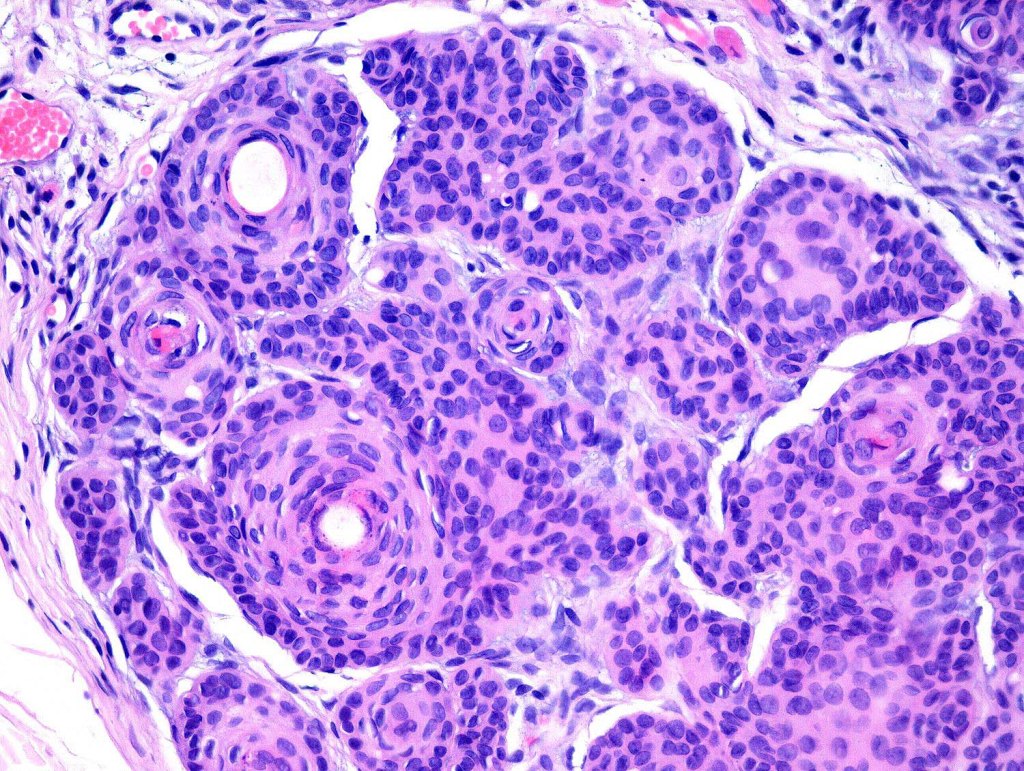

•Keratocysts showing infundibular keratinization i.e.with a granular cell layer

•Solid epithelial islands

•Fibrovascular stroma